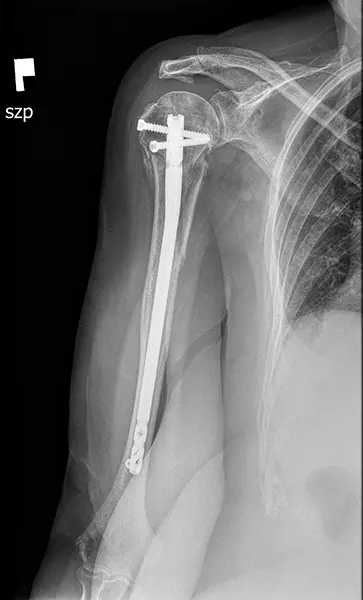

W przypadku złamań górnej części kości ramiennej, istnieje kilka technik, które można zastosować. Mogą to być szpilki, płytki ze śrubami, same śruby lub gwoździe (metalowe pręty). Istnieje również możliwość rekonstrukcji guzowatości kości, co jest szczególnie ważne w przypadku naprawy ścięgna mankietu rotatorów.

Każdy chirurg ma swoje preferencje i doświadczenie w zakresie wyboru techniki osteosyntezy. W niektórych przypadkach preferowane może być gwoździowanie śródszpikowe, gdzie wprowadza się gwoździe do głowy kości ramiennej i umieszcza się je w zagłębieniu trzonu kości strzałkowej. To pozwala na przymocowanie guzowatości do głowy kości ramiennej i trzonu za pomocą śrub oraz czasami szwów kostnych i ścięgnistych.